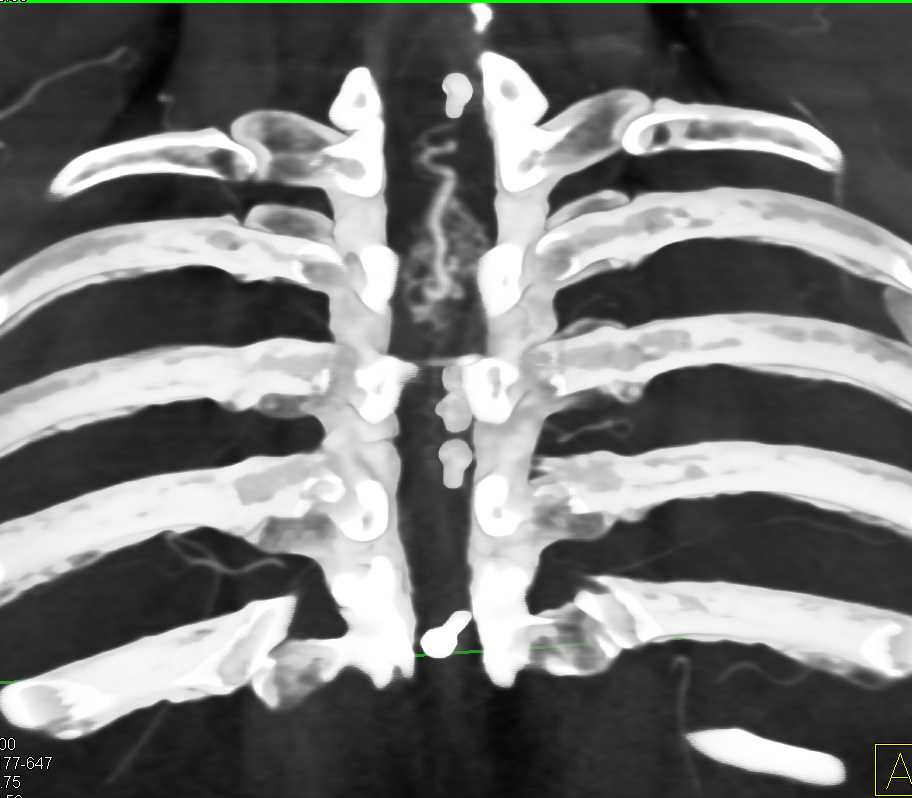

Keutel syndrome (KS) with Cartilage Calcification in the Earlobes